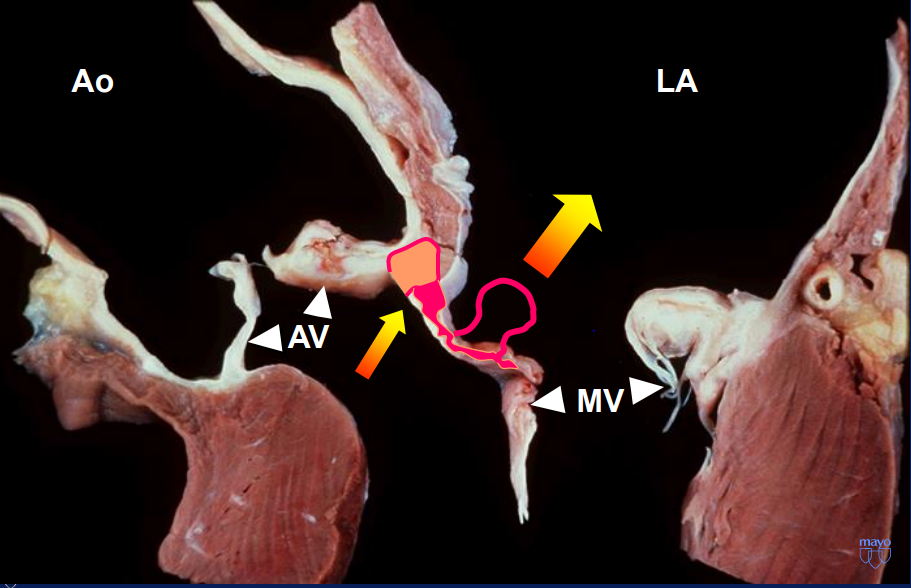

Mitral Aortic Intervalvular Fibrosa MAIF

Fibrous region of the heart that connects the anterior mitral leaflet to the posterior aortic root and communicates with the left ventricular outflow tract

MAIF Pseudoaneurysm